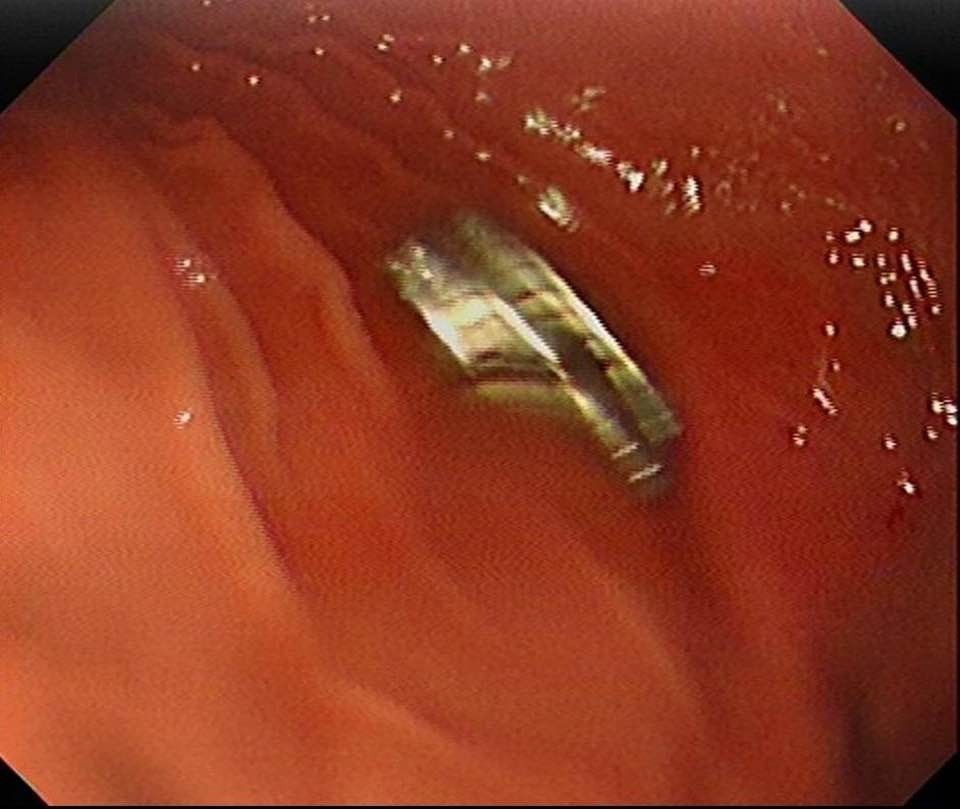

Fırat Üniversitesi Çocuk Gastroenteroloji Hepatoloji ve Beslenme Bilim Dalı Başkanı Prof. Dr. Yaşar Doğan, hastayı acilen ameliyata aldı. Yapılan endoskopik işlemle çocuğun yemek borusuna ve mide girişine yapışan 19 mıknatıs başarılı şekilde çıkarıldı.

Prof. Dr. Doğan, “Mıknatıslar uzun süre yemek borusunda kalınca ciddi zedelenmeler oluşmuştu. Ancak müdahale sayesinde kalıcı bir hasar oluşmadan hastamızı sağlığına kavuşturduk” dedi.